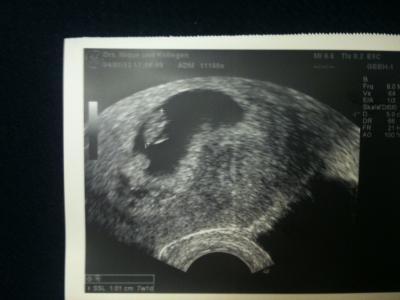

Juhuuuuuuu! Endlich Frauenarzt Termin gehabt! Alles supi. Nur bin ich weiter als gedacht! 7+5 statt 7+1 wie ich dachte. Herzle schlägt auch schon. Das ist jetzt mein viertes Kind und ich freu mich jedes Mal wieder sooooooo arg! Es ist einfach ein Wunder

Bild zu Eeeendlich FA Termin - Forum für August - Mamis